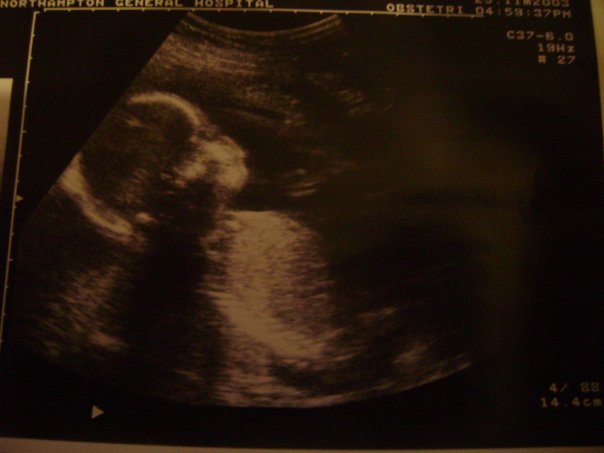

- Going for the 12 week scans and seeing my son and daughter for the first time was lovely, it made both pregnancies feel more real and it put my mind at ease knowing everything was okay.

- The 20 week scans were equally as exciting and finding out they were pink and blue!